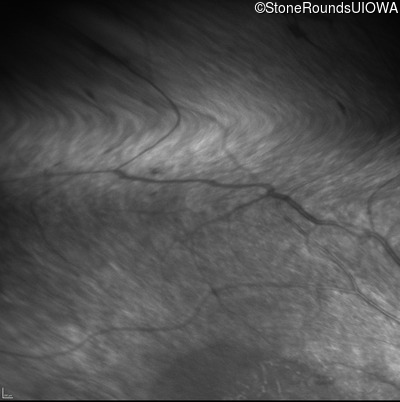

Infrared Fundus Photograph - Left - Light Perception

Exemplar